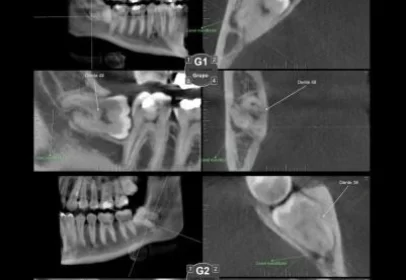

A tomografia da Articulação Temporomandibular (ATM) é um exame de imagem detalhado que avalia as estruturas ósseas da região, como o côndilo da mandíbula e a fossa mandibular do crânio. É uma...

A tomografia computadorizada é de grande importância para a avaliação da articulação temporomandibular (ATM) e para o diagnóstico das Disfunções Temporomandibulares (DTMs). Ela permite que o dentista...